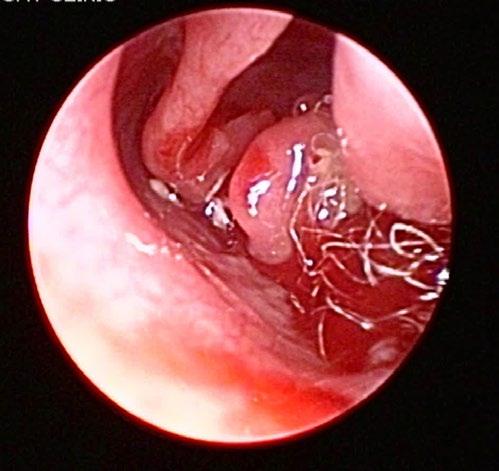

Marcy presented back to us on the 15th of July 2025 for a nasal endoscopy. Inflamed lymphoid tissue and mild haemorrhage was visualized via retroflexed nasopharyngeal endoscopy (Figure 1)

A left rostral nasal endoscopy was then performed, which allowed visualization and removal of a white fibrous foreign body using a 1mm endoscopic biopsy instrument (Figure 2)

2. Anterior rhinoscopy reveals fibrous material caught between inflamed turbinates and surrounded by some fresh blood